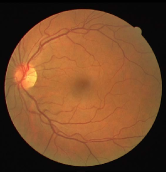

As pointed out in recent works [15, 17], a good semantic segmentation network should learn multi-level features. Further, it should have multiple stages with different receptive fields to learn more inherent features from different scales. FCN, taken as an example, uses skip connections to fuse multiple stages outputs, as well as the HED network, in which a series of side-output layers are added after each stage in VGGNet. The HED network was first proposed for edge detection, and further used for image-level vessel segmentation in recent studies [6, 16], with significant performance. However, our experimental results show that such network architecture is not appropriate for vessel segmentation directly. Figure 1 provides such an illustration. Reasons for this phenomenon are straightforward. On one hand, the side-output of the first layer often contains too many noises. On the other hand, the features produced by the last side-output layer are too coarse due to information loss of pooling operation. Obviously, the inaccurate vessel map of side-output1 and side-output4 should have negative impacts on the final segmentation result.

With the deepening of DSN network, the receptive field of each side-output layer gets larger, which makes the corresponding vessel map much blurrier as observed from the first row in Figure 1, especially for side-output4. These observations inspired us to pass low level fine semantic information to high levels to alleviate the blurring situation.

Bottom-top short connections aim to refine high-level segmentation results. However, we can observe from the first two rows in Figure 1 that the vessel map generated by the first side-output layer contains too many noises while the map generated by the last side-output could capture the main vessel structure. Therefore, we propose delivering high-level structural information to the first side-output layer to reduce its noises. We implemented this kind of information delivery by a top-bottom short connection from conv4 to feat_conv1, which can been seen in Figure 4. We first convolved the last convolution of conv4 using 1 convolution kernels with size 33. Then the obtained feature map are up-sampled 8 to get feat_4_1. The information (feat_4_1) passed from conv4 are concatenated with feat_conv1 to form feat_conv1_fuse (see Figure 5). At last, one hand hand, we perform a 11 convolution operation on feat_conv1_fuse to get the information (feat_1_2) delivered to feat_conv2. On the other hand, we performed convolution operation with a kernel size of 11 and sigmoid transformation for feat_conv1_fuse sequentially to obtain the segmentation result (side 1). At last, side 1 is compared with the ground truth to get the loss of the first side-output layer.

In addition, we can observe from Figure 1 that the side-output1 and side-output4 of the BTS-DSN were more accurate compared with those of the DSN.